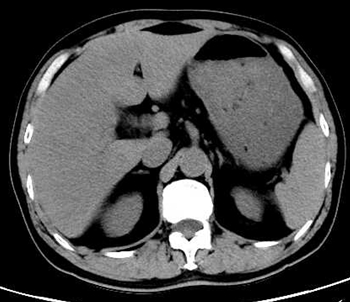

今晨零点左右上厕所后再发畏寒发热,家属发现其口唇发紫、呼吸急促,遂来本院急诊。腹部CT平扫提示肝内积气(图 2)。收住急诊抢救室,急查腹部增强CT,考虑肝脓肿致肝脏破裂(图 3)。

| 图 3 患者冠状位增强CT提示肝内胆管积气(箭头所指处) |